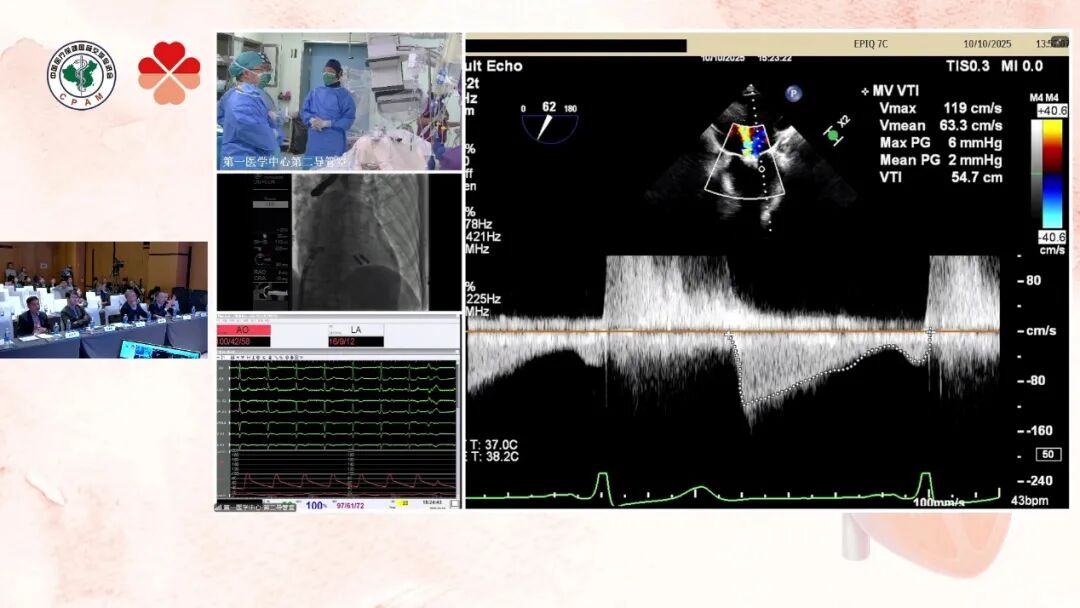

患者为59岁男性,主诉间断胸闷10年,近1月出现喘憋。既往病史显示,2015年因冠脉三支病变接受过3枚支架植入。术前超声心动图提示左房及左室扩大,二尖瓣重度反流,前叶长度29mm,后叶长度22mm,二尖瓣AP径40mm,反流束集中在2区,肺静脉逆流明显。术中,团队首先进行房间隔穿刺,确保进入左心房的路径安全且位置理想。随后,依次送入两枚TEER夹子,通过实时超声引导和透视监控,精确调整夹合高度和位置,使夹子牢固抓住二尖瓣前叶与后叶,同时最大限度减少残余反流。每次夹合后,术者通过评估瓣口面积和瓣膜形态,确认夹子位置和效果后再进行下一步操作,最终成功完成两枚夹子置入,术后超声显示二尖瓣反流明显减轻,瓣口形态良好。

术前超声评估二叶瓣病变及房间隔

术中调整夹合程度

术后平均跨瓣压差仅2mmHg